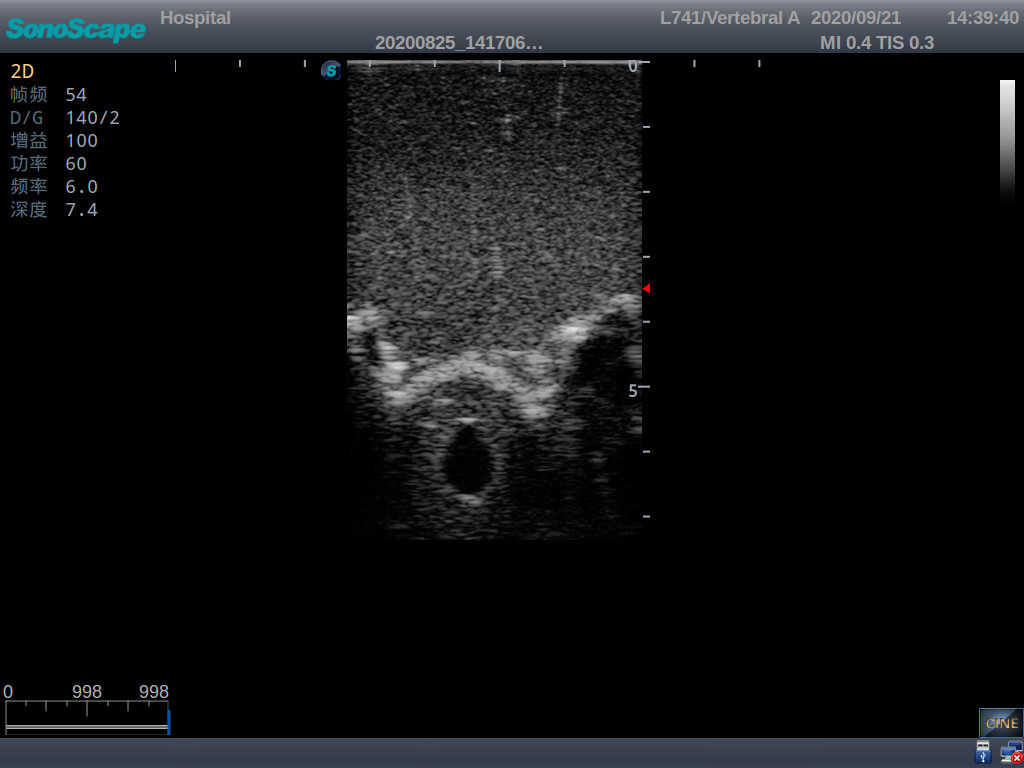

Adult Lumbar Puncture Ultrasound Training Model

This model is an ideal choice for ultrasound-guided adult lumbar puncture training with true-to-life skin feel and touch, accurate anatomical structures as well as real clinical ultrasound images. Realistic resistance to needle tips and correct landmarks provide excellent hands-on experience.

Accurate anatomical structure of L1-L5 and the vertebral canal

2)  Real clinical ultrasound images

3)  Compatible with various real ultrasound machines